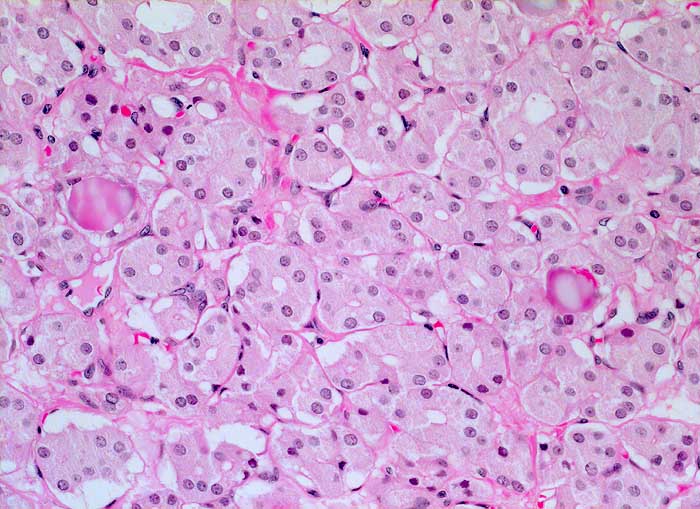

Mikrofollikuläres Schilddrüsenadenom (toxisches Adenom)

Das Adenom besteht aus monomorphen kleinen Follikeln mit hochprismatischem aktiviertem Epithel. Die Follikel enthalten wenig oder gar kein Kolloid.

Makroskopisch solitärer bunter Knoten von 6cm Durchmesser.

Zytologisch wurde aufgrund der zahlreichen vorhandenen Epithelien und einzelner Mikrofollikel eine follikuläre Neoplasie diagnostiziert.